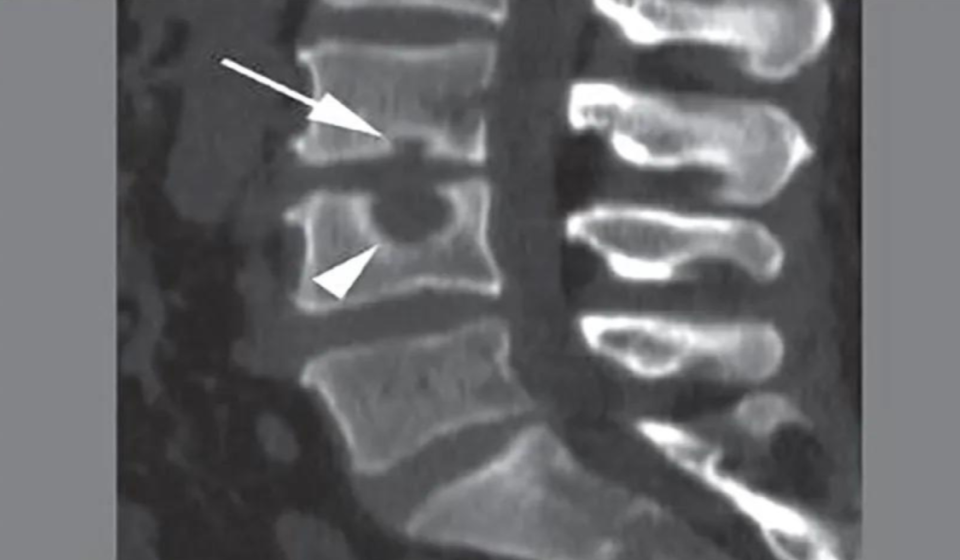

Schiacciamento vertebrale

Cause, sintomi e trattamento

Ernia di schmorl

Dalla diagnosi al trattamento

Frattura vertebra

Cosa fare e Cosa non fare